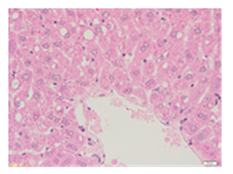

Liver wet weights of all rat groups showed no significant differences (Table 8). According to histochemical hematoxylin and eosin (H&E) staining, treatment with the highest dose of MPE (1000 mg/kg BW) did not result in morphological changes in the liver tissue (B) when compared with DI water treatment (A). Obviously, CCl4 induction (ip)/DI water treatment (po) caused hepatoxicity, which was indicated by a severe degree of fatty changes and fatty cysts in the liver tissue (C), whereas pretreatments of silymarin (100 mg/kg BW, po) effectively decreased the degree of fatty changes and fatty cysts in the liver when compared with the CCl4/DI water group. Indeed, MPE (250 and 1000 mg/kg BW, po) lowered the degree of lipid accumulation in the liver; inversely, MPE (500 mg/kg BW, po) exhibited a severe degree of lipid accumulation. Apparently, taking paracetamol (2 g/kg BW) induced a severe degree of hepatic necrosis when compared with rats that had not received the treatment. Similarly, pretreatments of silymarin (100 mg/kg BW, po) and MPE (250 and 1000 mg/kg BW, po) revealed a mild degree of hepatic necrosis, while MPE (500 mg/kg BW, po) revealed a moderate to severe degree of hepatic necrosis. Accordingly, the findings imply that the consumption of MPE (1000 mg/kg BW) was not harmful to the liver of healthy rats, while MPE (250 mg/kg BW) did improve fat deposition in the livers of CCl4-fed rats and offered protection against liver cell damage in paracetamol-fed rats.

Wet weight values (mean ± SD) and H&E staining of liver from rats with hepatotoxicity induced by CCl4 and paracetamol.

Each liver was embedded in a paraffin block, cut into slides, deparaffinized, and stained with hematoxylin and eosin (H&E) dye. The liver tissue sections were examined in terms of their histopathological status and photographed under light microscopy by a qualified expert clinical pathologist at the Department of Pathology, Faculty of Medicine, Chiang Mai University, Thailand.